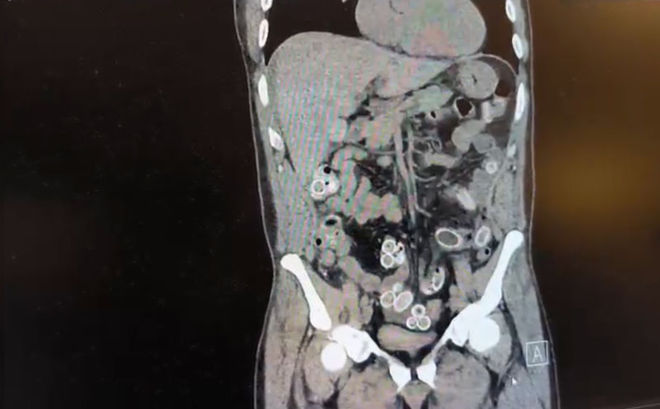

DHA'daki habere göre yapılan muayenenin ardından Cüneyt G.’nin tomografisi çekildi. Şüphelinin mide ve bağırsaklarında yabancı madde tespit edilmesi üzerine hastane yetkilileri durumu polis ekiplerine bildirdi.